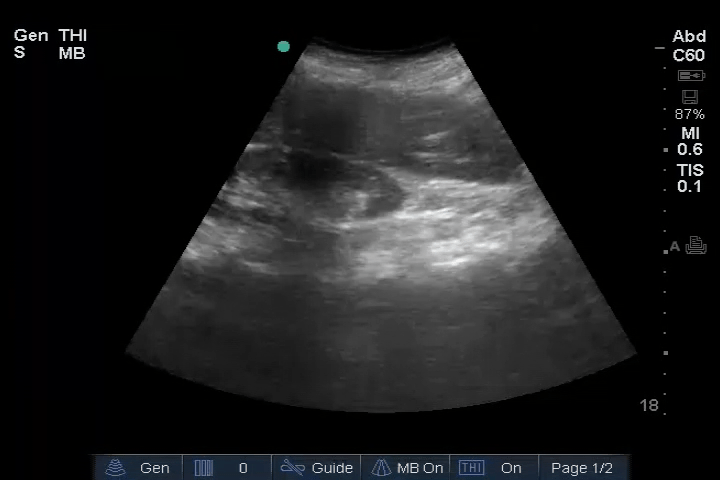

10_Heart_SC – Dilated RV, RA embolus

Heart: Dilated right ventricle (RV), most clearly visualized in the PSAX view. An embolus is visible in the right atrium (RA).